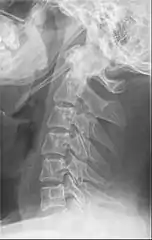

Radiograph, lateral view showing elongated stylohyoid process and stylohyoid ligament ossification

Radiograph, lateral view showing joint-like formation in ossified stylohyoid ligament

Imaging is important and is diagnostic. Visualizing the styloid process on a CT scan with 3D reconstruction is the suggested imaging technique.[11] The enlarged styloid may be visible on an orthopantogram or a lateral soft tissue X ray of the neck.